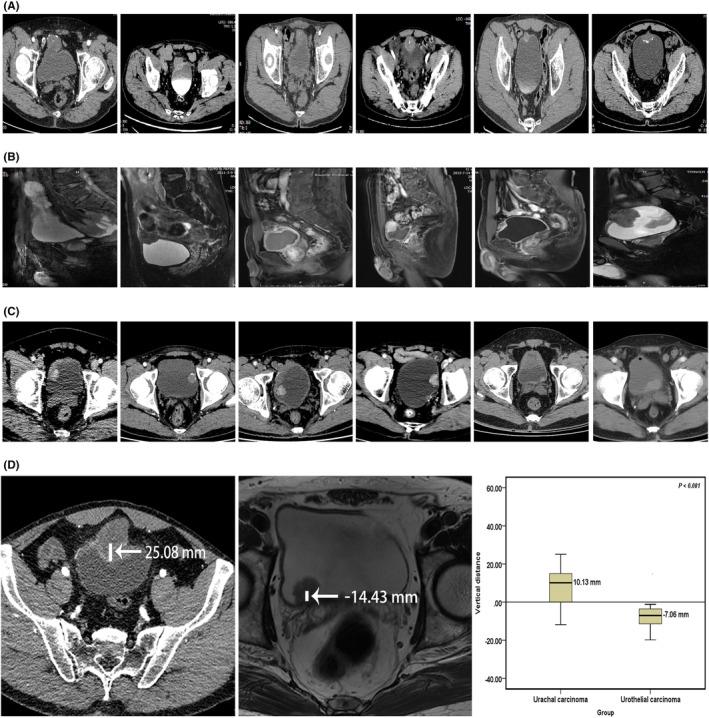

A total of 37 patients with UrC were enrolled in this study, including 30 males and seven females, with a median age of 52.00 (44.50-63.50) years. Imaging and cystoscopy suggest that UrC grows primarily outside the bladder cavity and is found in the middle line of the dome or anterior wall of the bladder. There was a significant difference in tumor location between the UrC group and the UCa group (10.13 mm vs. -7.06 mm, p < 0.001). Immunohistochemistry revealed that CK20 and CDX-2 were both diffusely and strongly positive. β-catenin was strongly positive in cytoplasm and membrane, but negative in nuclear staining. Carcinoembryonic antigen (CEA) and carbohydrate antigen 72-4 (CA724) expression levels were significantly higher in the UrC group than in the UCa group (p < 0.05). In the diagnosis of UrC, the area under the curve (AUC) of CEA combined with CA724 was the greatest. FISH's sensitivity in diagnosing UrC (5/7, 71.43%) was not significantly different from that of UCa (71.43% vs. 77.50%, p = 0.659). Imaging examination has the highest sensitivity and specificity among the accuracy evaluation of different diagnostic methods.

本研究共纳入 37 例 UrC 患者,男 30 例,女 7 例,中位年龄 52.00(44.50~63.50)岁。影像学和膀胱镜提示 UrC 主要向膀胱腔外生长,位于膀胱穹窿或前壁中线。UrC 组与 UCa 组肿瘤位置比较,差异有统计学意义(10.13 mm 比-7.06 mm,P<0.001)。免疫组化结果显示 CK20 和 CDX-2 均弥漫强阳性,β-连环蛋白胞质和膜强阳性,核染色阴性。癌胚抗原(CEA)和糖类抗原 72-4(CA724)在 UrC 组的表达水平明显高于 UCa 组(P<0.05)。在 UrC 诊断中,CEA 联合 CA724 的曲线下面积(AUC)最大。FISH 诊断 UrC 的敏感度(5/7,71.43%)与 UCa 比较差异无统计学意义(71.43%比 77.50%,P=0.659)。不同诊断方法准确性评估中,影像学检查的敏感度和特异度最高。